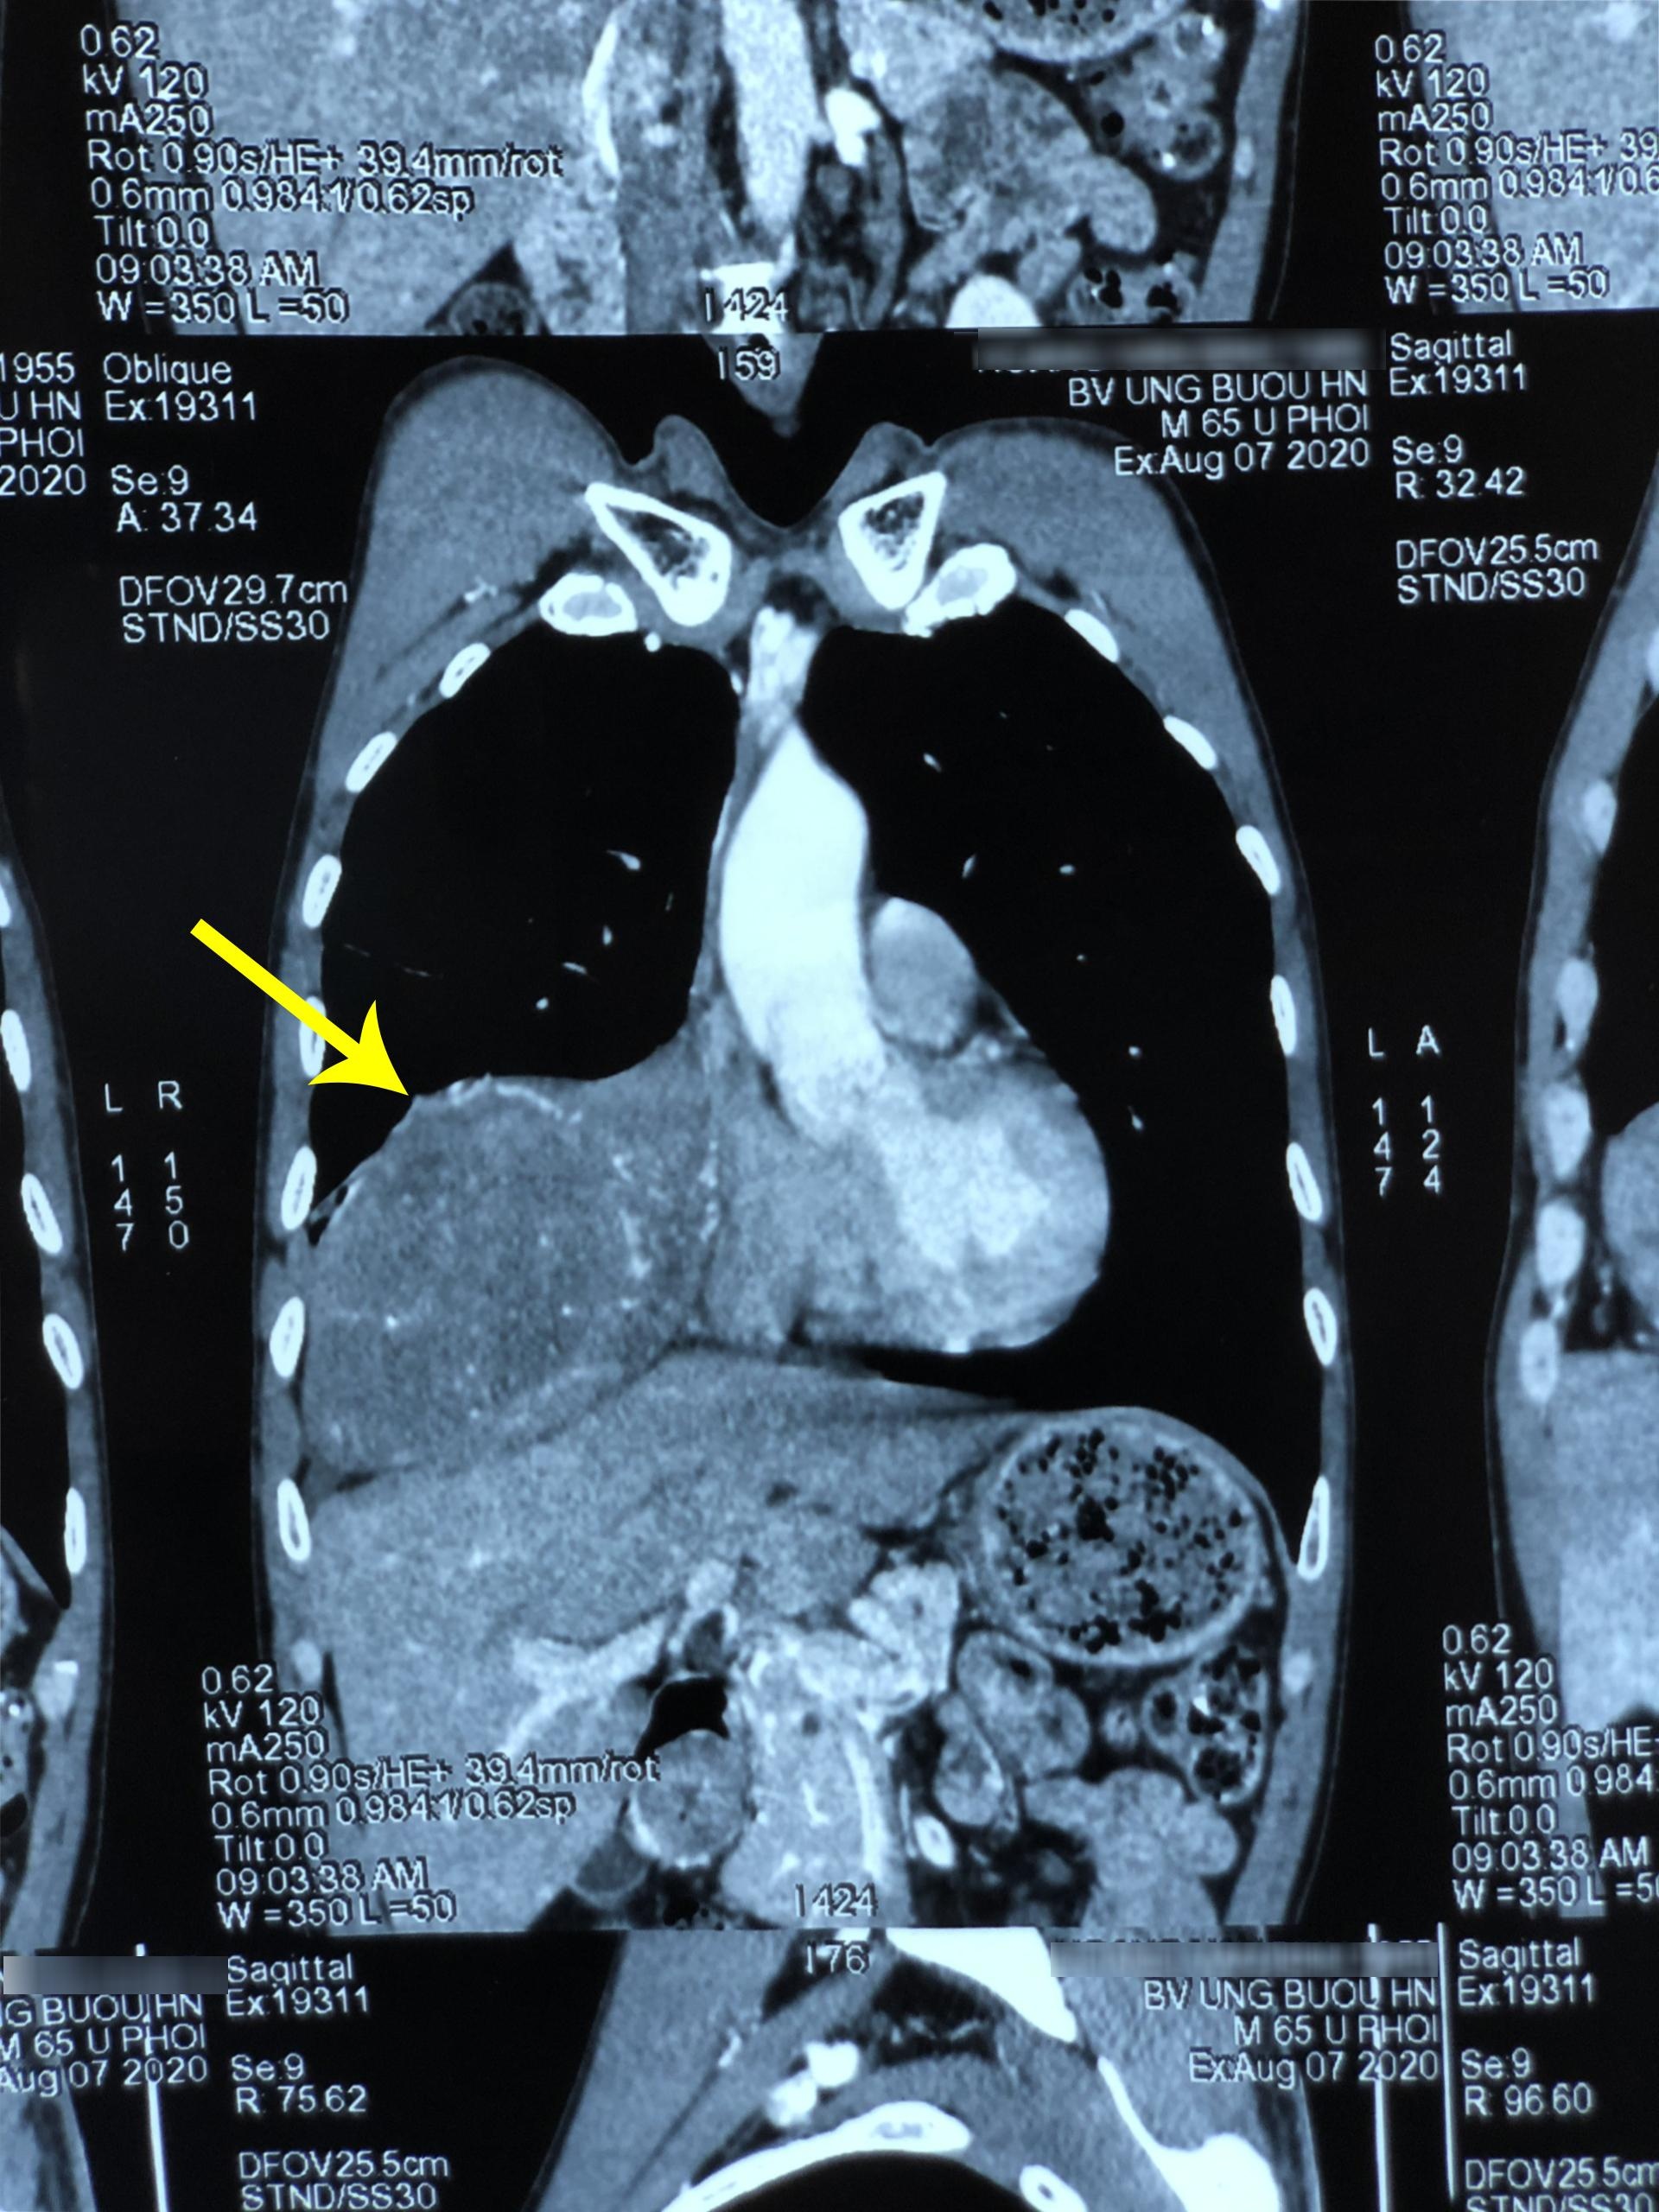

Kết quả cộng hưởng từ và cắt lớp vi tính cho thấy phổi phải của bệnh nhân có khối u kích thước 11x18 cm. Khối u này nằm ở vị trí xuất phát của màng phổi vùng vòm hoành, đè ép các thùy phổi, xung quanh bị tổn thương dạng đông đặc gây xẹp phổi.

Khối u chiếm 2/3 thể tích phổi phải. Ảnh: BVCC.

Các bác sĩ nhận định khối u có thể phát triển lớn, chèn ép gây đau, tức ngực, khó thở, xẹp phổi phải, thậm chí ảnh hưởng tới nhịp tim.